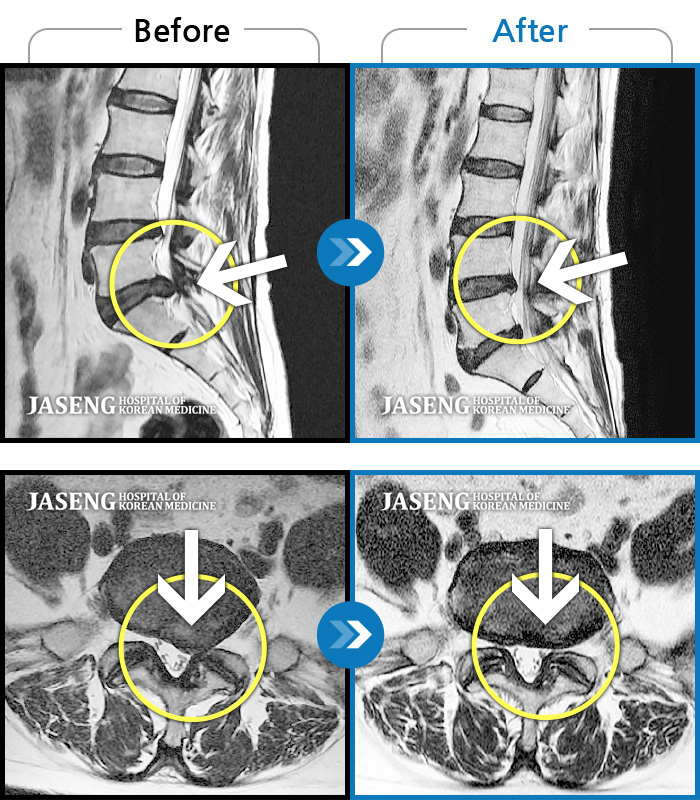

요추 추간판 탈출증을 진단받은 입원 환자의 보완대체의학 통합치료의 장기 효과

Before

After

통증 및 우측 엉치 우측 종아리 땡기는 통증이 심하여 일상생활이 안되는 상태로 내원하셨던 분입니다.

2023.11.21 ~ 2024.06.05